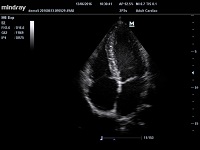

Клинические изображения Mindray M5 new